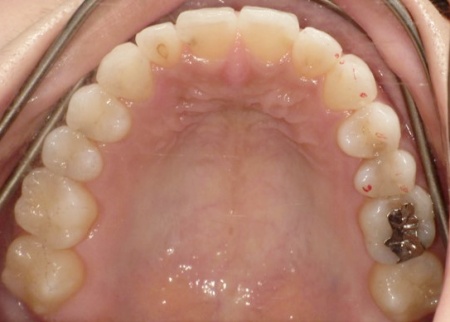

20代女性 受け口と噛み合わせのずれをマウスピース型矯正装置による部分矯正で改善した症例

拝見したところ、前歯の噛み合わせが通常とは逆の受け口の状態でした。また噛み合わせが横にずれており、お顔を正面から見ると上下の歯の真ん中が一致していません。

このまま放置すると見た目に悪影響が出るだけでなく、前歯で食べ物を噛み切ることが難しくなって胃腸の負担が増えたり、顎関節に過剰な負荷がかかって痛みが出たりするおそれがあります。

以上のことから、矯正治療で歯並びと噛み合わせを改善する必要があると診断しました。